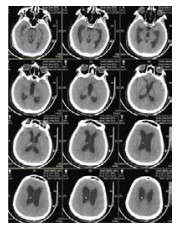

将分流管压力降为0.5后的第6天,该患者复查头颅CT和意识水平均无明显改变;后经分流储液囊穿刺脑脊液外引流,每日引流量150 mL,持续10 d,仍无明显改变。再将脑脊液外引流量增至300 mL/d,患者行为学稍有变化,开始出现刺激后头部转动、手部摸索活动,眼球能视觉追踪。复查头颅CT示脑室形态略缩小。因此,在此基础上再次手术将分流管由原来的抗虹吸可调压管更换为非抗虹吸可调压管,压力设为1.0。患者意识水平进一步改善,术后第4天复查CT示脑室较前缩小(图 2),其大小形态接近正常。随访一年,患者生活能自理,E-GOS 5分。

| 图 2 病例1更换分流管后第4天头颅CT |